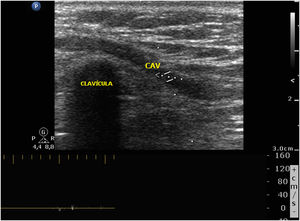

Paciente que ingresa en Unidad de Cuidados Intensivos por neumonía derecha, se canaliza catéter venoso central de inserción periférica (PICC) para tratamiento intravenoso. En radiografía de tórax el catéter no desemboca en aurícula derecha y sigue un trayecto a nivel clavicular (fig. 1). Al 6.° día de ingreso se retira PICC, presentando una celulitis en el cuello a nivel de la yugular izquierda. Realizamos ecografía vascular donde se objetiva una trombosis venosa desde la zona de canalización del PICC en la vena mediana cefálica izquierda (MC), que progresa por la vena cefálica hasta yugular externa por un tramo de comunicación anómala venosa supraclavicular (figs. 2 y 3).